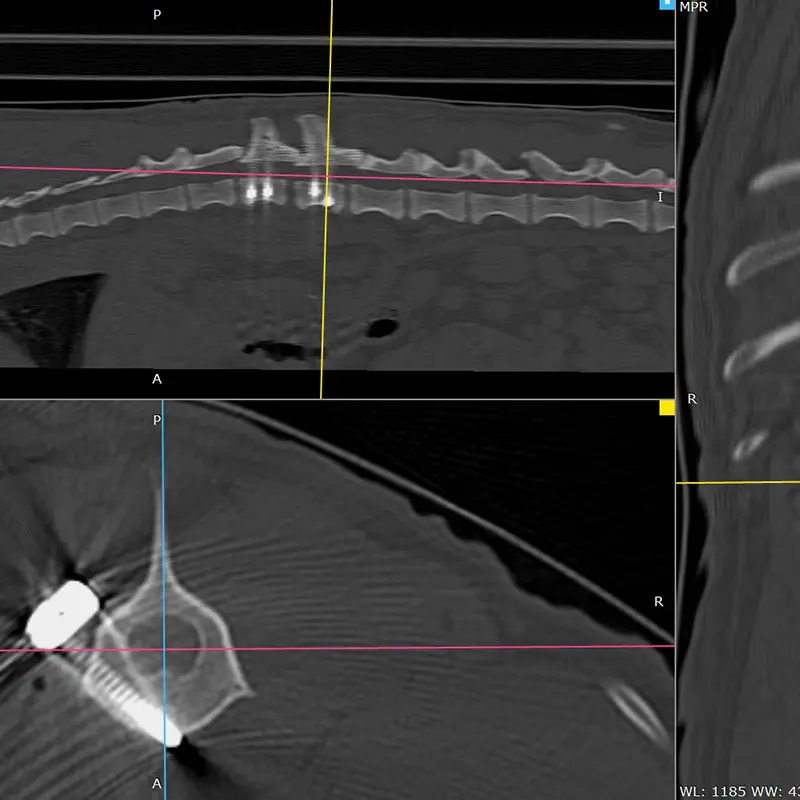

We have been using the system for years, and clinical experience greatly supports its reliability, even in difficult, challenging situations. It is excellent for stabilizing the spine, especially in the thoraco-lumbar region. If the connecting rod is placed ventrally from the articular processes, the screws are placed in the vertebral body at a 45-degree angle at the base of the transverse processes, so that they grip the largest possible bone material. (see CT images). Up to 2 clamps can be attached to a vertebral body from one side. Compared to other, more complex, multi-piece spinal stabilization systems, it is thinner and fits better on the surface of the bone. The screw axis is located ont he side of the axis of the connecting rod (the rod and the screw are not located on top of each other), the clamps can be rotated and slid, so that the largest possible bone stock can be freely accessed during surgery.

In our case, we stabilized the T13-L1 vertebral luxation of a 4-year-old dachshund, where the ligament system of the vertebral body was damaged during a car accident.